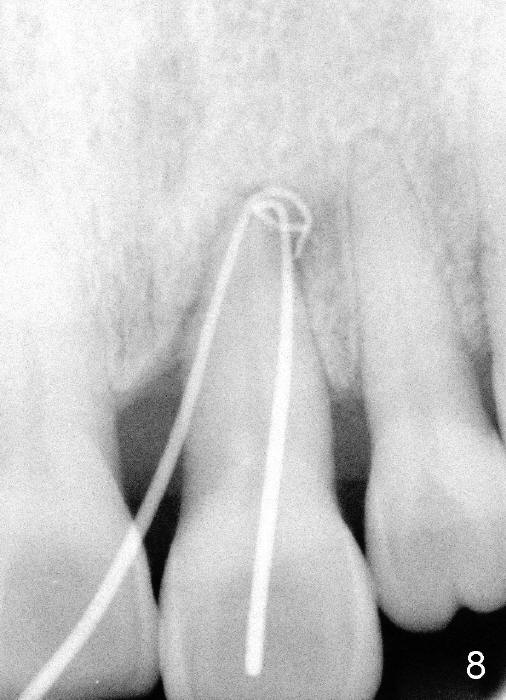

A 60-year-old lady had an abscess mesial to #9 six years ago (Fig.1,2 <), treated as a perio lesion by laser (Fig.3) and osseous surgery without bone graft (Fig.6, followed by CT exam revealing semi-circumferential bone loss (Fig.4,5). When the perio treatment failed, attention was paid to endo aspect (Fig.7-9). In fact the pulp was found to be vital when access to root canal therapy was made. As expected, the treatment failed again. The palatal fistula persisted. The infection was suspected to be a source of remote immediate implant site (#30). The tooth #9 was extracted. It appears that there is a semilunar crack line in the linguomesial root (Fig.12). When the socket healed 2 weeks post extraction (Fig.10), the #30 buccal defect was debrided with bone graft. There was no bone resorption 4 weeks post extraction (Fig.11); a 4.5x17 mm implant was placed (Fig.13-15). An immediate provisional was fabricated (Fig.16-18). Fig.19,20 were taken 3 months post implantation and 7 months post cementation, respectively. Dense bone forms around the implant coronally 4 years 5 months post cementation (Fig.21), while the gingiva is healthy palatally (Fig.22) and buccally (Fig.23).